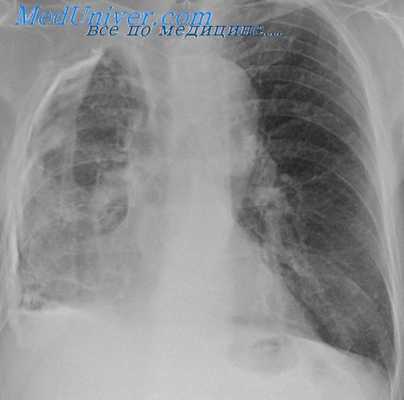

Традиционным при выполнении торакальных операций считается проведение однолегочной механической вентиляции легких с интубацией главного бронха (ГБ) в условиях миоплегии, со своими минусами, присущими искусственной вентиляции легких (ИВЛ) и миорелаксации. Анестезиологическое пособие в торакальной хирургии по праву признается одним из наиболее сложных из-за специфических трудностей, с которыми сталкивается анестезиолог [12]. Главное — легкое на стороне операции по абсолютным либо относительным показаниям должно быть временно выключено из вентиляции и коллабировано. Искусственная однолегочная вентиляция чревата развитием тяжелых расстройств гемодинамики и газообмена (гипоксемия) вследствие резкого увеличения внутрилегочного шунтирования и нарушения вентиляционно-перфузионных отношений, увеличением нагрузки и перегрузкой правого и левого отделов сердца, гипергидратацией легочного интерстиция, гиперкапнией и тяжелыми метаболическими расстройствами в виде дыхательного и метаболического ацидоза и т. д. [13—16]. Развивающиеся при этом патофизиологические процессы, их профилактика и коррекция являются основной проблемой торакальной анестезиологии. Проведение подобных операций с сохранением спонтанной вентиляции не создает особых проблем торакальному хирургу в виде «ограничения свободы действий», так как за счет атмосферного давления при открытии плевральной полости легкое в той или иной степени коллабируется (рис. 3).

Хотелось отметить, что, несмотря на неселективную интубацию после создания открытого пневмоторакса, под действием атмосферного давления легкое спадалось, его структуры хорошо визуализировались, что не мешало работе хирурга.